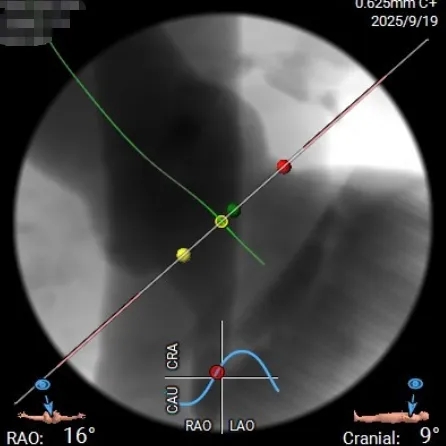

投照体位及瓣环角度分析

Angio

右窦中心

左右重合

右无重合

外周入路评估